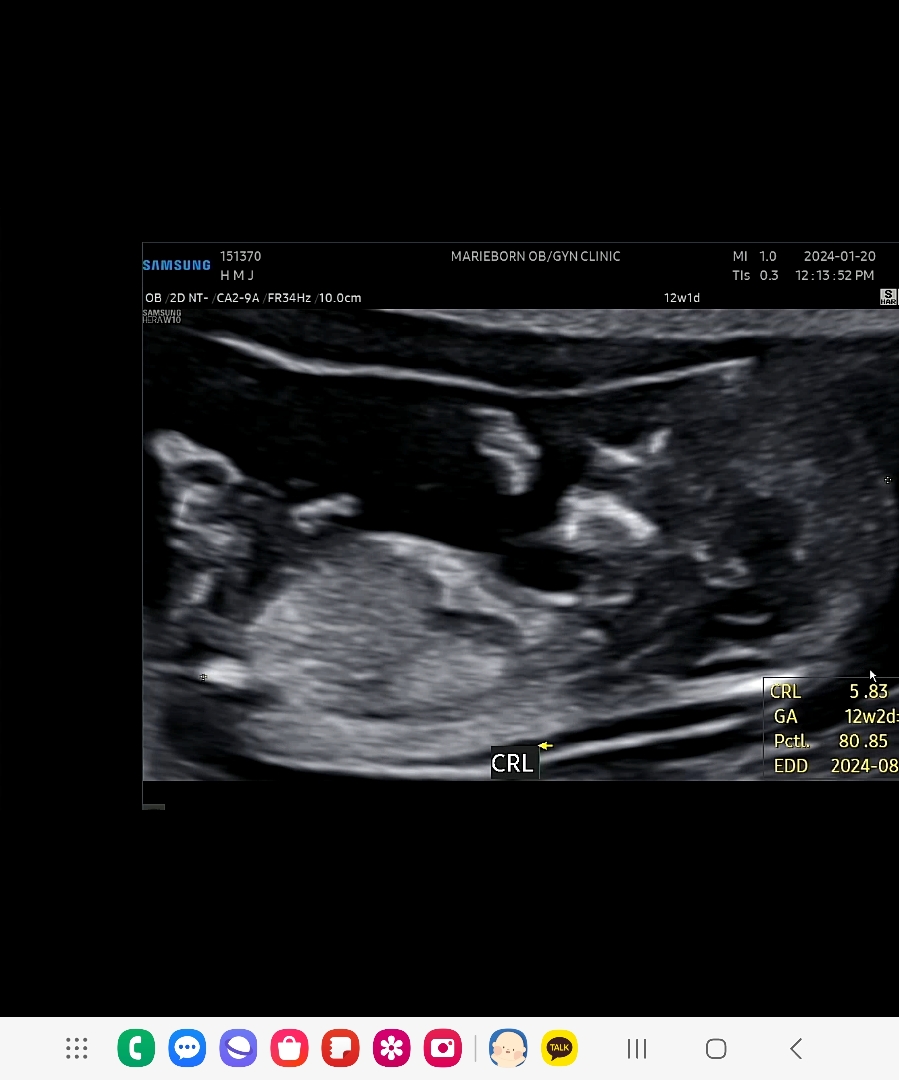

12주 기형아검사

첫입초인데 얼굴도보여주고 손발이 쏘큐티하네욧ㅠㅠ 저도 성별이 넘넘궁금해지네욥 아계속봐도 귀여워용 각도법 보이시나요 제눈엔 안보여오오ㅠ